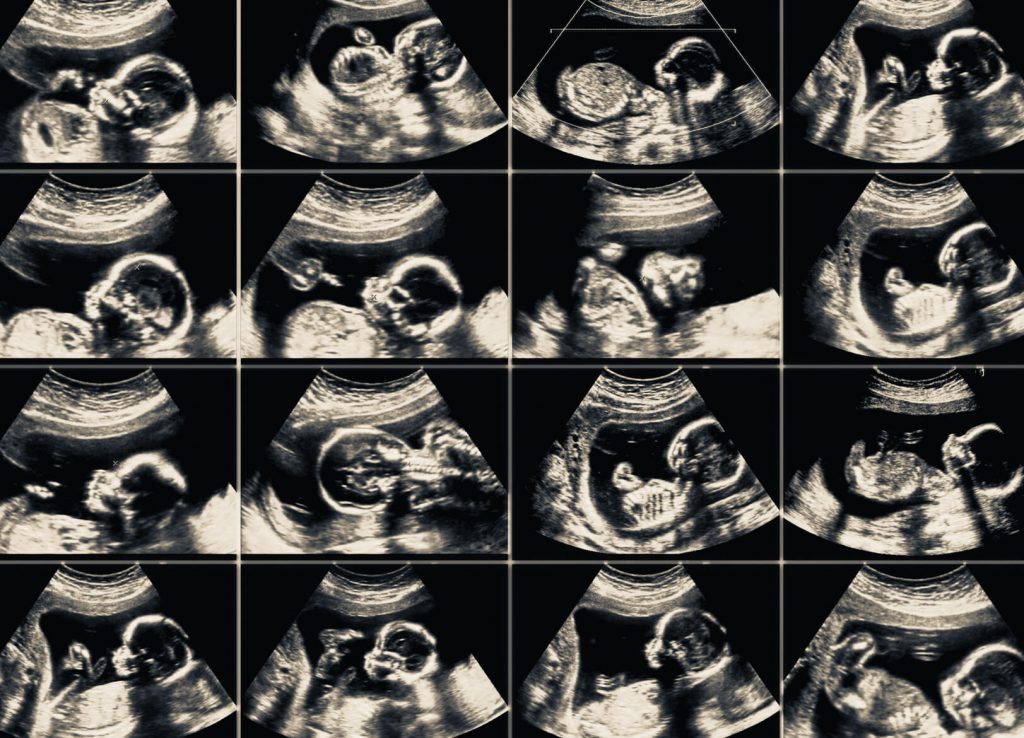

Badania USG w ciąży

- USG II trymestru (pomiędzy 18-22 tygodniem ciąży) – najlepiej po skończonym 20 tygodniu ciąży (wtedy rozwój wszystkich struktur ośrodkowego układu nerwowego jest zakończony, a płód dostatecznie duży, aby w pełni ocenić jego anatomię) (więcej o badaniu USG II trymestru, tzw. „USG połówkowym” znajdziesz tutaj).